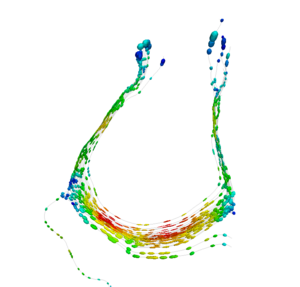

Our implementation uses spectral clustering, a method for grouping data using eigenvectors of a data affinity matrix. This image gives an overview of the method. On the left example input tractographic paths are shown (these were created by manually seeding in the 3D Slicer). The center image shows an embedding of the tracts as points in 2D, where the distance between points is related to their shape similarity. This embedding was calculated as an intermediate step during spectral clustering. The image on the right shows the final output in the 3D Slicer, where tractographic paths are colored by cluster membership.